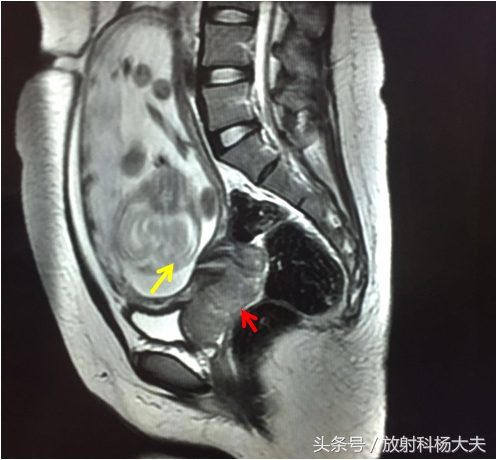

红箭所指的地方就是病变,还能够看见肚子里的宝宝(黄箭)。而且经过进一步的分析,病变已经累及阴道及直肠,提示为宫颈癌的晚期!

对于局部病变的显示,MRI无疑是最好的。因此临床上进行术前分期的时候都选择MRI检查。宫颈基质的低信号环是否完全是宫颈癌I期与II期的分界标志,完全的低信号环说明癌灶局限在宫颈,可排除有宫旁组织的侵犯。如低信号的基质环被高信号的肿瘤破坏,出现中断或是突破,提示肿瘤已经侵犯宫旁组织,属于II期。肿瘤累及阴道下1/3、盆腔、直肠等周围脏器,为III 、IV期。